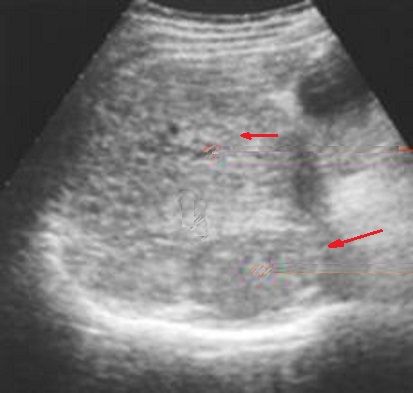

Image TDM des

metastase hepatiques : Sur la TDM a sans

preparation , aspect lesionaire souvent isodense . Les

metastase colorectale souvent hypovasculaire : lesions est

hypodenses au temps portale. Les metastases du rein souvent

hypervasculaire : lesion est hyperdense au temps arteriel

Metastase hypovasculaire du

cancer colique : Aspect lesionaire des metastase est

hypodensse au temps portal |

Metastase hypervasculaire

d'un cancer du rein : Aspect lesionaire hyperdense au temps arteriel

|